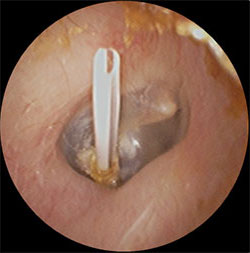

また、このような状態を繰り返すようであれば鼓膜を切開したあとに小さいチューブを挿入して滲出液が溜まらないようにする方法もあります。もちろん、これらの処置をする場合は患者様(お子様の場合はお父様・お母様)とご相談の上、治療方針を決めていきます。当院では小児の鼓膜チューブ挿入も通常の外来で実施可能です。(場合により連携する総合病院へご紹介させていただきます。)

・上記の滲出性中耳炎の鼓膜に小さな切開をいれ、内部の液体を吸引し、鼓膜チューブを挿入

・左図の処置後から1週間後、鼓膜内側には液体は溜まっておらず、正常の鼓膜の色である